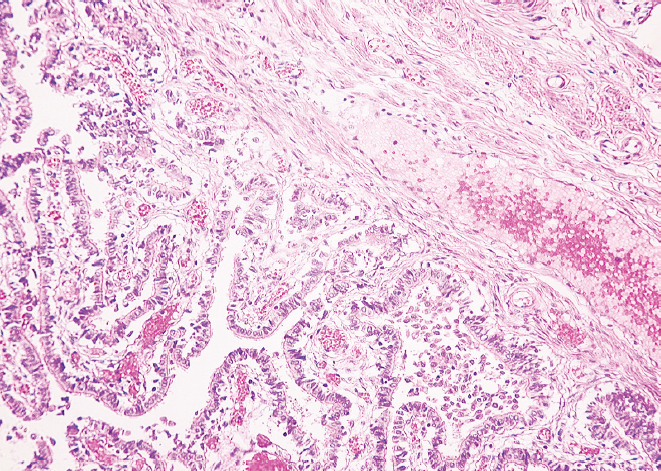

Гистологическое исследование препаратов показало, что в молодом возрасте слизистая оболочка перешейка и воронки маточных труб образует множественные продольные складки. Она представлена однослойным столбчатым эпителием и собственной пластинкой, которая образована рыхлой соединительной тканью. По ходу маточной трубы реснитчатые и секреторные эпителиоциты (экзокриноциты) располагаются неравномерно — реснитчатые преобладают в воронке маточной трубы, а секреторные — в области ее перешейка. Мышечная оболочка состоит из циркулярного и продольного слоев (рис. 1, 2).

Рис. 1. Фрагмент перешейка маточной трубы женщины в возрасте 25 лет. Окраска гематоксилином и эозином, увел. ×10